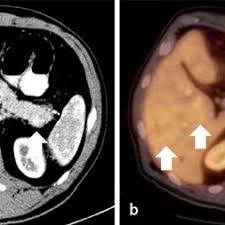

Abb 1 8 Neuroendokriner Tumor Mit Lebermetastasen Konventionelles Ct Download Scientific Diagram